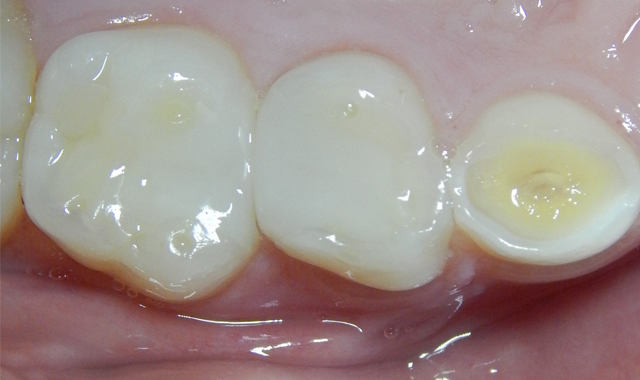

Leaving dentin moist (dentin should never be dried anyway) TheraCal LC is applied and light-cured. Because TheraCal LC incorporates hydrophilic monomers, it spreads better on moist dentin and adheres after light curing (Fig. 6). The alkaline pH and calcium release, very similar to ProRoot MTA (Dentsply), stimulates dentin formation and inhibits bacterial growth.44,45

The etched dentin was hybridized with ALL-BOND UNIVERSAL® adhesive (BISCO), a seventh-generation adhesive, and was restored with a resin-based dual cure (bulk fill) composite (Fig. 6). After removal of the rubber dam, the patient thanked me for making him “numb.” He claimed it was the first time he had been anesthetized for dental care. His mother was unaware that he had never received anesthesia for treatment, and had thought that he was just being “too sensitive.” The patient has returned for recare appointments and the teeth have remained asymptomatic (Fig. 7).

Fig. 6 Fig. 7